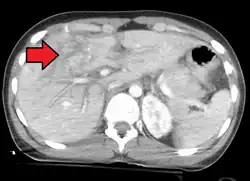

Grade 4 liver laceration

Imaging, such as the use of ultrasound or a computed tomography scan, is the generally preferred way of diagnosis as it is more accurate and is sensitive to bleeding, however; due to logistics this is not always possible.[6] For a person who is hemodynamically unstable a focused assessment with sonography for trauma (FAST) scan may take place which is used to find free floating fluid in the right upper quadrant and left lower quadrant of the abdomen. The FAST scan however may not be indicated in those who are obese and those with subcutaneous emphysema.[7] Its speed and sensitivity to injuries resulting in 400mL of free-floating fluid make it a valuable tool in the evaluation of unstable persons. Computed tomography is another diagnostic study which can be performed, but typically is only used in those who are hemodynamically stable.[7] A physical examination may be used but is typically inaccurate in blunt trauma, unlike in penetrating trauma where the trajectory the projectile took can be followed digitally.[8] A diagnostic peritoneal lavage (DPL) may also be utilized but has limited application as it is hard to determine the origin of the bleeding.[9] A diagnostic peritoneal lavage is generally discouraged when FAST is available as it is invasive and non-specific.[7]